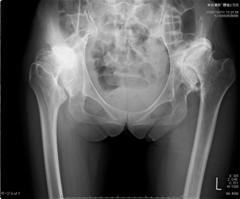

(3) X線フィルムによる術前計画との違い

| Ⅰ: 座標系を立てる | |

|

![]() ![]() |

| Ⅱ: 可動域シミュレーション機能 | |

![]() |

| Ⅲ: 奥行きを考慮した立体計画・骨移植例などの例に有効 | |

どの術式を選択するか?

(1) 両側骨移植併用

(2) 両側高位設置

(3) 片側骨移植併用